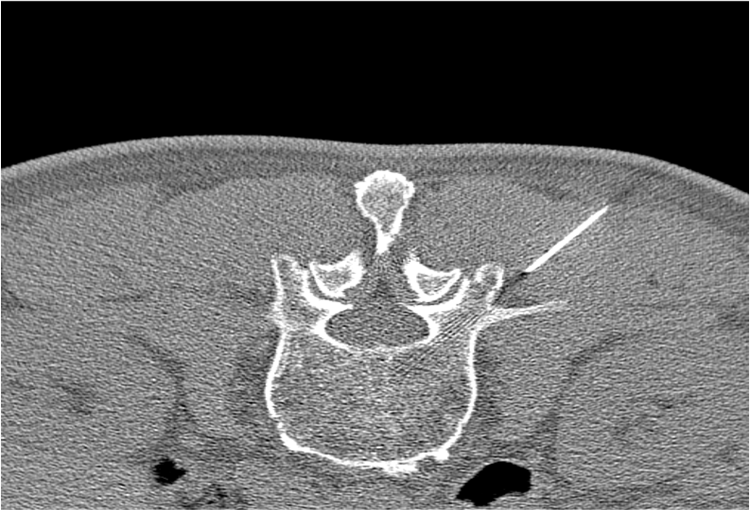

Before and After Denoising

120 kV / 30 mAs / 1mm

Before FBP (Noise 150) VS After ClariCT.AI (Noise 49) 67% Denoising